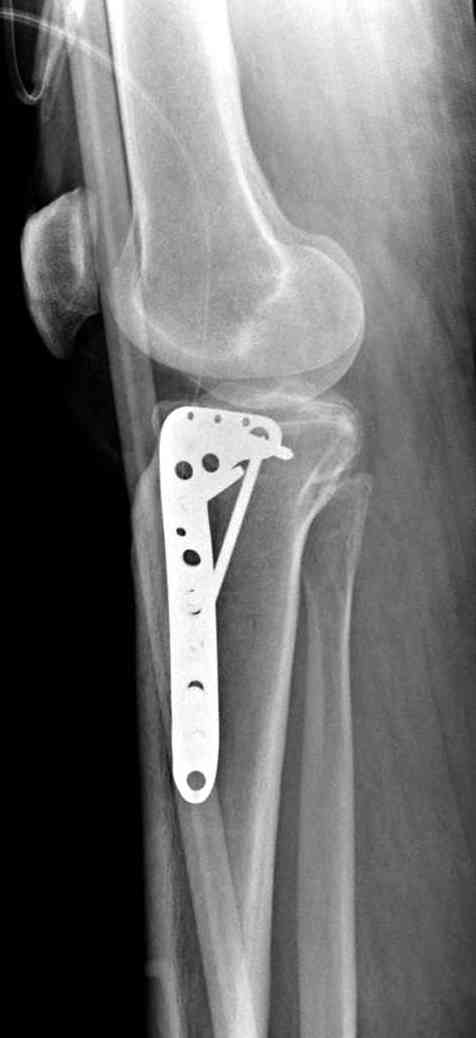

Нет, малоберцовый внизу, фиксацию проводим на верхнем эпифизе, где твердая кость. Задача состоит

в том, чтобы создать арматуру из нескольких проведенных шурупов на эпифизе.

Это техника применяется, когда имеется

центральная импрессия, а при ипрессии с краевым переломом - после приподнимания импрессии опорная (Butress) пластина, как на снимке.